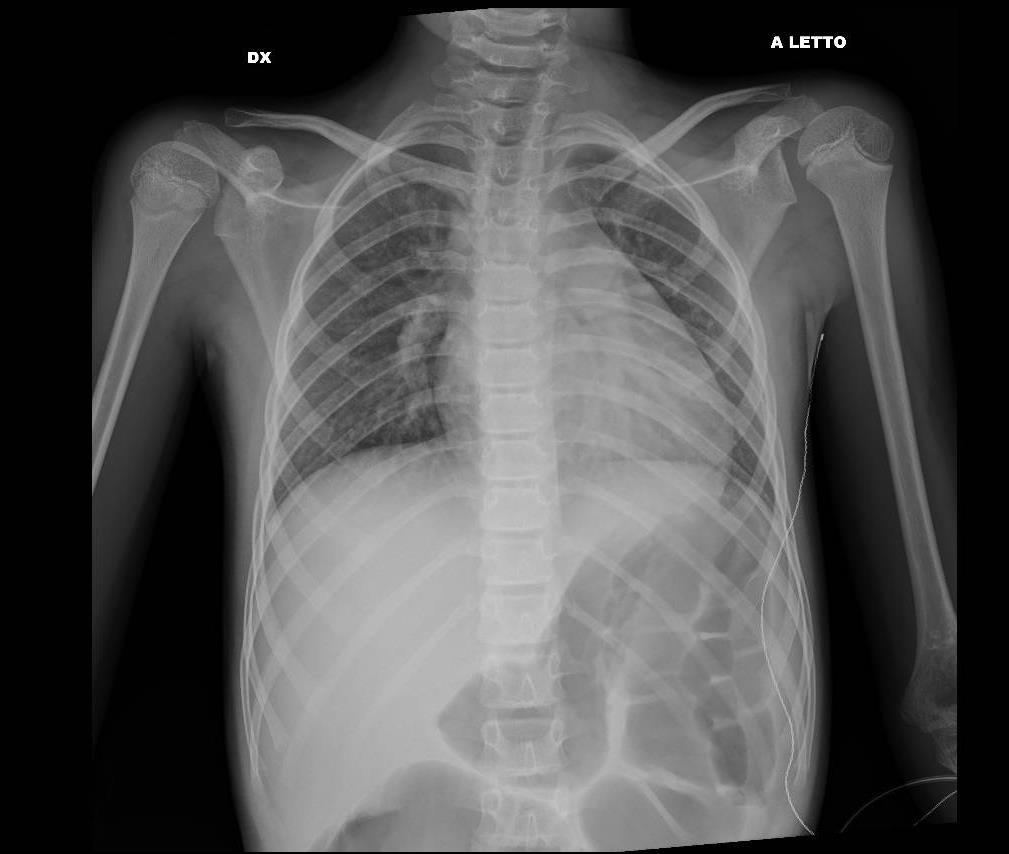

Imaging of Covid 19 infection in children CXR 8 38% 3% 51% 8%

Consolidation 35%

Collapse 3%

PeriBronchial thickening

51%

Hyperexpansion 7%

Effusion 4%

Imaging of Covid 19 infection in children CXR 9 C O V I D

Birmingham

Covid 19 CXR Imaging of Covid 19 infection in children